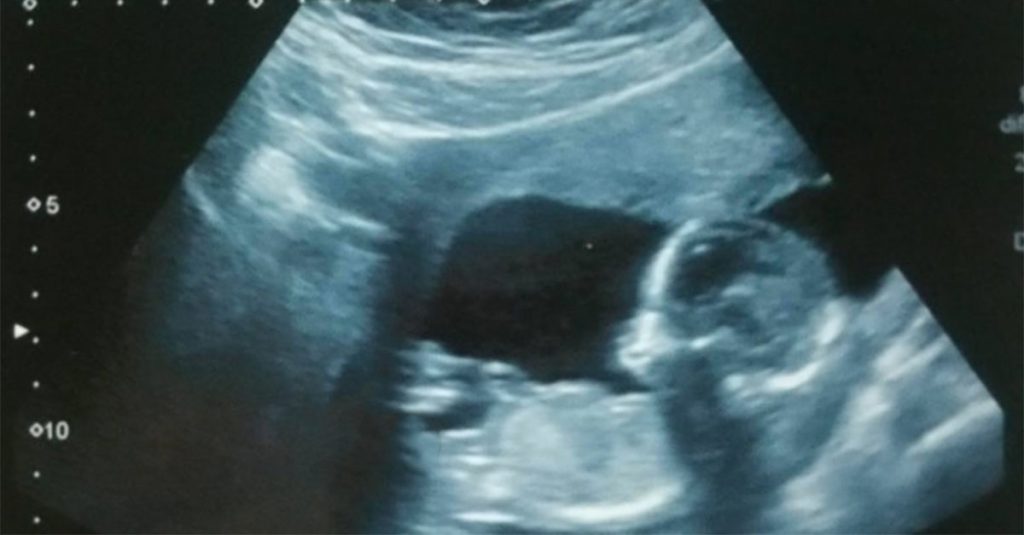

Jamie Jenkins e seu marido Jacob Lang ficaram em estado de choque quando os médicos viram a ultrassom de 16 semanas de seu filho, onde o nanismo havia sido diagnosticado. “É loucura que eu e Jacob carregamos o mesmo gene que causa nanismo”, disse Jamie.